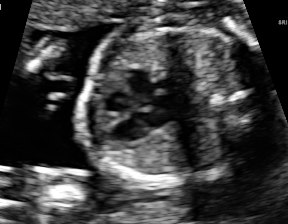

| 4CH | Abdominal | Femur | Lips | LVOT | |

| SF | |||||

| SC | ![]() |

![]() |

We demonstrate the practical applicability of our method on a challenging medical application, the classification of standardized fetal ultrasound (US) views during prenatal screening. In many countries, US imaging is clinical routine for prenatal health care. The classification of standardized views is important for a consistent, cross-institutional identification of possible abnormalities [47]. Early detection of pathological development can inform following treatment and delivery options [55, 25]. DNNs have shown promising performance to support this task [2]. However, ultrasound images are often hard to interpreted [40]. Anatomical structures have inconsistent appearance [2] and contain different orientations and shapes of anatomical landmarks [1]. Labeled training data is often insufficient as annotating medical images requires significant expertise and is prohibitively expensive in both time and labor. Manifestation of acoustic shadows [17, 44] as shown in Fig. 2(a) as well as different imaging devices as shown in Fig. 2(b) can lead to a domain shift problem for vanilla DNN classifiers. Exploring domain adaptation in fetal US enables DNN classifiers to be effectively utilized on a wider range, which supports identification of abnormalities from varying data sources. This can benefit prenatal healthcare.

We evaluate the proposed method on two fetal US standard plane classification tasks, where the domain shifts are respectively caused by shadow artifacts (Fig. 2(a)) and different image acquisition devices (Fig. 2(b)). For both tasks, images from source and target domains are unpaired and collected independently. We show the key results in the main paper and detailed implementation, network architectures as well as more results in the supplemental Appendix.

The fetal US dataset consists of 2D fetal US images sampled from 2694 2D US examinations with gestational ages between weeks (iFIND Project 555http://www.ifindproject.com/ ). Eight different US systems of identical make and model (GE Voluson E8) were used for the acquisitions to eliminate as many unknown image acquisition parameters as possible. Six different anatomical standard plane locations have been selected by an experienced sonographer, including Four Chamber View (4CH), Abdominal, Femur, Lips, Left Ventricular Outflow Tract (LVOT) and Right Ventricular Outflow Tract (RVOT). The images have additionally been classified by an expert observer as shadow-containing or shadow-free. In this experiment, the source domain contains shadow-free images (see Fig. 2 (b) SF) while the target domain has shadow-containing images from less favorable imaging conditions (see Fig. 2 (b) SC). Training data consists of all six standard planes from the source domain as well as Abdominal, LVOT and RVOT from the target domain. We aim to separate anatomical features (categorical features) and shadow artifacts features (domain features) to obtain generalized anatomical features for achieving high performance of standard plane classification on (4CH, Femur and Lips from target domain). Here, contains 4CH, Abdominal, Femur, Lips, LVOT and RVOT from the source domain and contains Abdominal, LVOT and RVOT from the target domain. Hyper-parameters to in Eq. 11 are for the proposed MIDNet model and is additionally for MIDNet+.